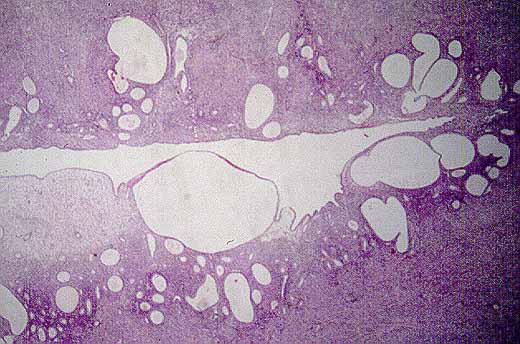

FIGURA 2.- Polipo endometrial (H-E x40) obtenido mediante legrado con glandulas quisticamente dilatadas.

figura 3

FIGURA 3.- (H-E x100) Magnificación de la imagen anterior en un area de decidualización estromal.